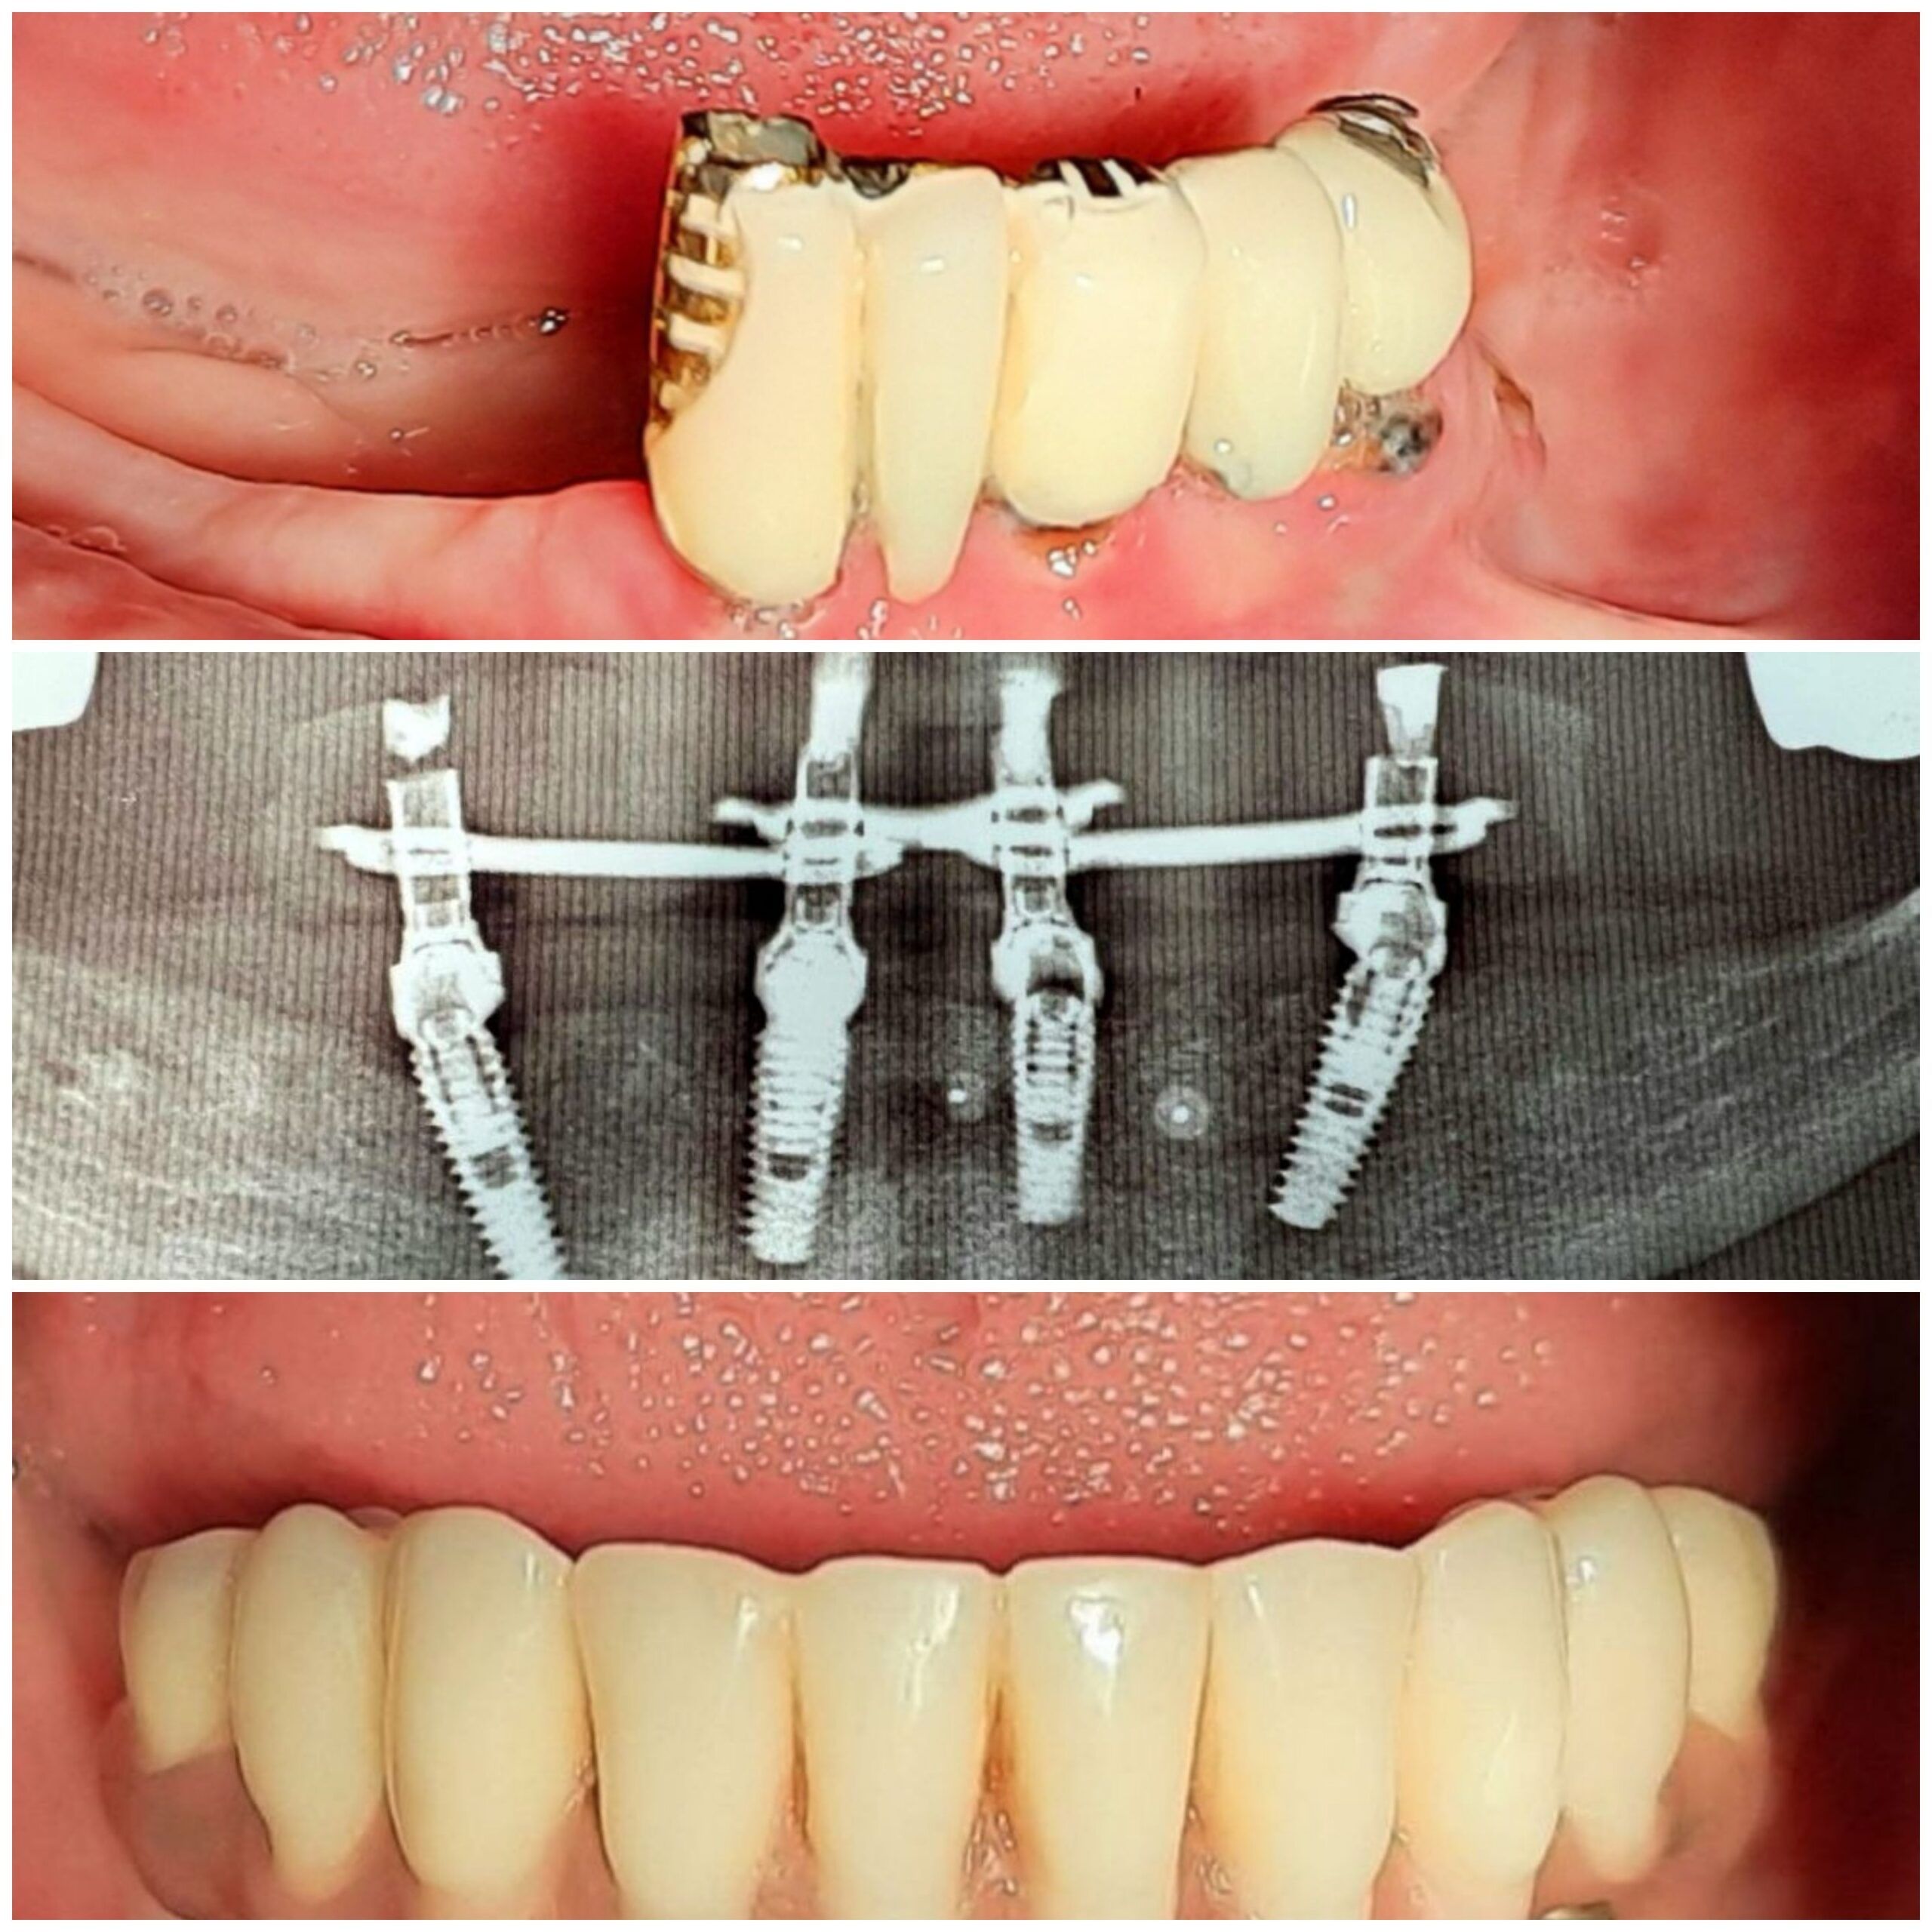

У стоматології МоканДент ми пропонуємо послуги з імплантації зубів, які допомагають відновити не лише вашу усмішку, але й функціональність зубів. Ми працюємо за світовими стандартами імплантації та встановлюємо корейські імпланти фірми OSSTEM.

Зубні імплантати – це сучасне та ефективне рішення для відновлення втрачених зубів, яке надає стабільний функціональний та естетичний результат. Вони інтегруються з природними тканинами щелепи, забезпечуючи надійне кріплення та повернення комфорту у щоденному житті.

Коронки та мости – це ефективні стоматологічні рішення, які використовуються для відновлення пошкоджених чи втрачених зубів. Коронки надають індивідуальний захист та відтворюють природний вигляд, а мости заміняють відсутні зуби, відновлюючи функціональність та естетику усмішки.